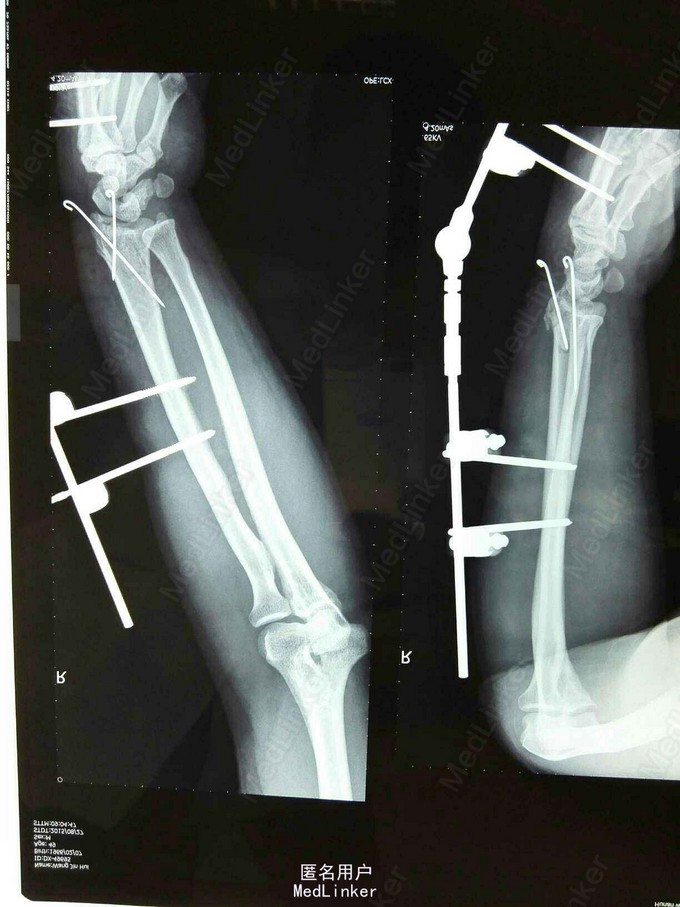

诊断:右桡骨远端粉碎性骨折。 治疗:暂予石膏托固定,五天后右腕部肿胀明显消退,在臂丛麻醉下行右桡骨远端骨折切开复位克氏针+外固定支架固定术。术后复查片见骨折对位对线良好,各指皮肤触痛觉无减退,活动可。